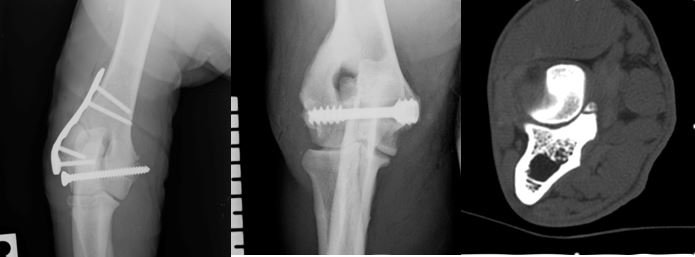

This course serves as an introduction to the management of some of the more common elbow pathologies currently encountered. It aims to guide attendees through the decision-making processes associated with elbow pain, focusing on the management of elbow dysplasia and humeral intercondylar fissure during the morning session.

In the afternoon, there will be a wet lab where attendees can practice screw placement. This session will also cover both medial and lateral approaches to the humeral condyle, as well as the placement of implants to effectively treat these fractures. This course includes both a wet and dry lab.